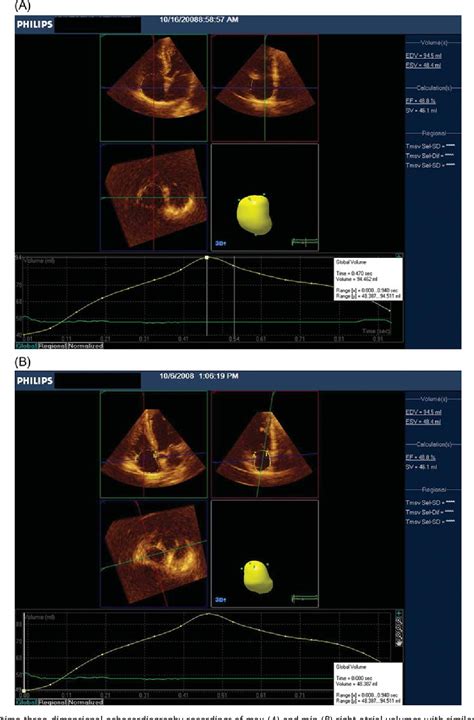

- Echocardiogram: The most common test, using ultrasound waves to create a real-time image of your heart’s chambers and valves.